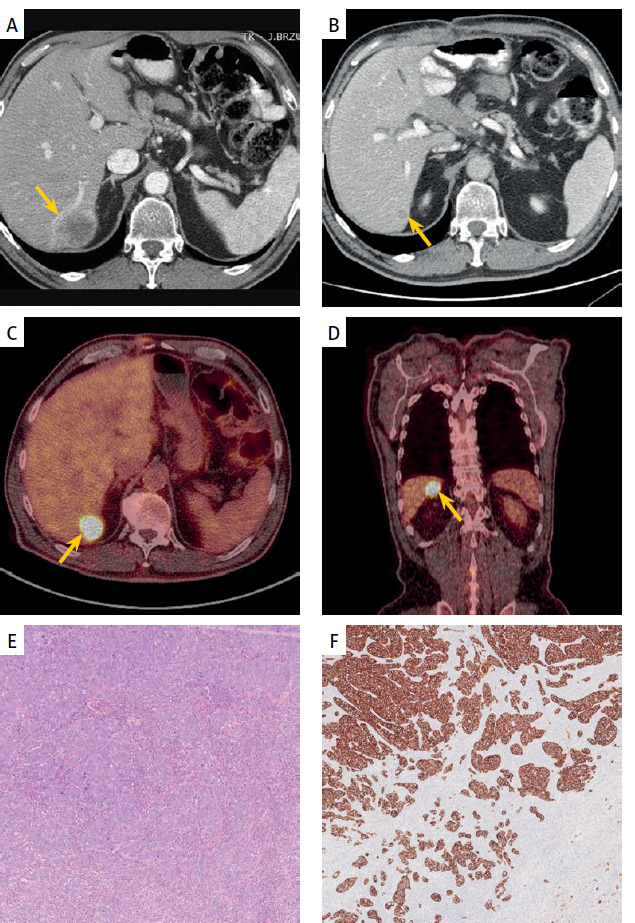

Multimodal treatment for long-term survival in ampullary adenocarcinoma metastatic to the liver.